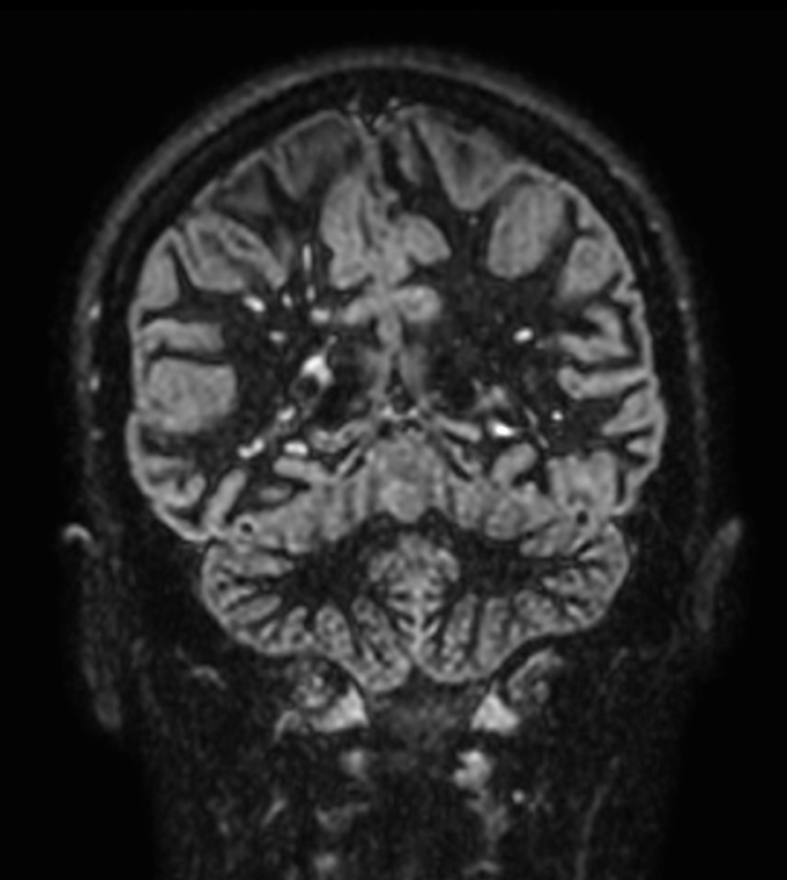

Patient with multiple brain lesions. ExamCard includes Compressed SENSE to shorten the exam time, 3D scans to acquire high resolution data in multiple directions in only one single scan and 4D-TRAK for dynamic contrast-enhanced MR Angiography enabling high spatial and temporal resolution simultaneously.

T2w TSE Compressed SENSE